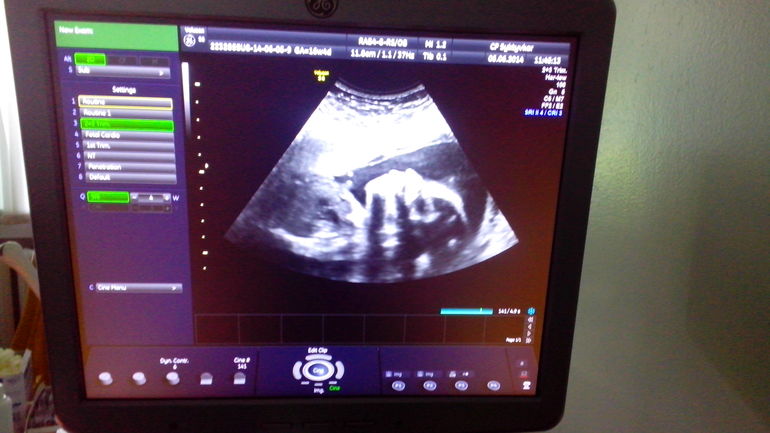

СамочувствиеВсем доброго дня,вот и началась 24 неделька,как у меня в животике поселилось чудо))))Сегодня ровно 5 месяцев(с 10 января)и ровно 23 акушерских недели))))Сынуля радует каждый день,активно бутузит меня изнутри по животу,иногда проводит серию ударов в одно какое-нибудь место)))Футболист наверно или боксер будет))))А я пока сама на дневном стационаре наблюдаюсь,т.к побаливает часто живот.Делали недавно УЗИ,смотрели рубец,так вот он в отличном состоянии,боли не из-за него.а еще на узи сфоткала сына и когда увидела его профиль,немного расстроилась:исчез мой курносый носик((((Появился "папин"прямой нос))))но может,это просто было так видно?)))На дневном только магнезию капают,остальные все анализы в норме,все хорошо.Записалась на 25.06 на УЗИ опять на 3Д))))Пост обязательно сделаю после.а так все вроде хорошо,только ужасно лень работать,уже одной ногой в декрете))))В декрет пока ставят на 29.07.а ПДР на 8.10.Посмотрим,что дальше будет.Ну и для отчета вот моя пузяка в 23 недельки и малышок-сынуля пару дней назад))))